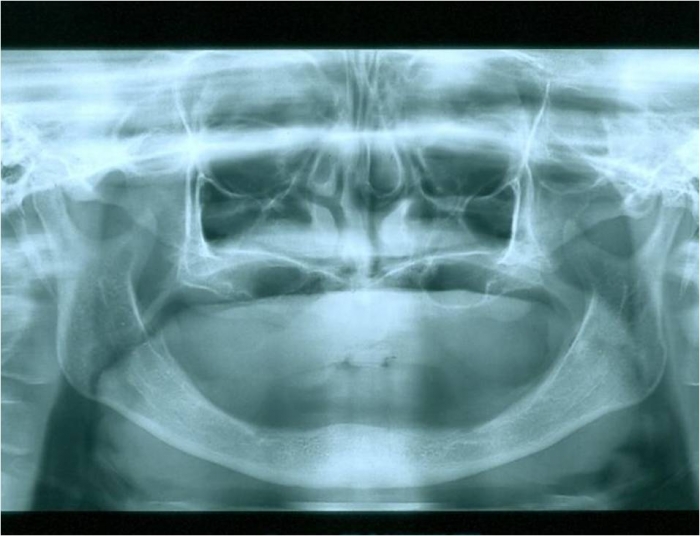

Raio x inicial